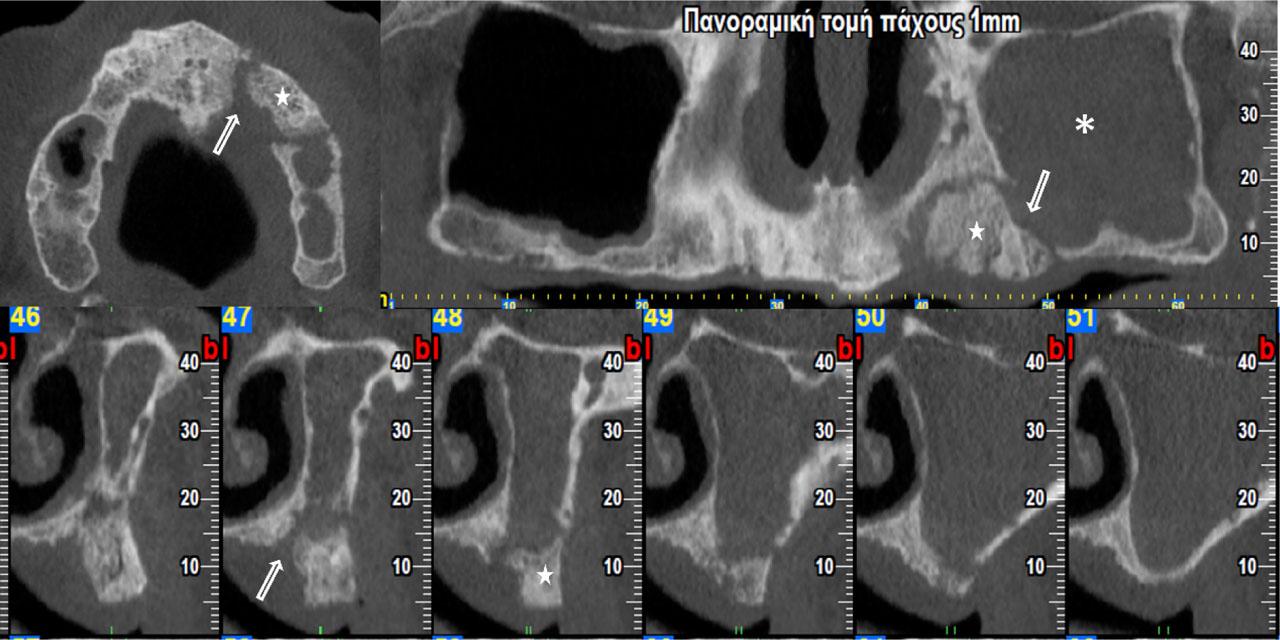

Figure 4:

Cone Beam Computed Tomography of a cancer patient, who received antiresorptives. Osteolytic areas (arrows) and bone sequestrum (stars) are observed in the maxilla. Fullness of left sinus is also seen (asterisks). Patient was diagnosed with MRONJ stage 3.